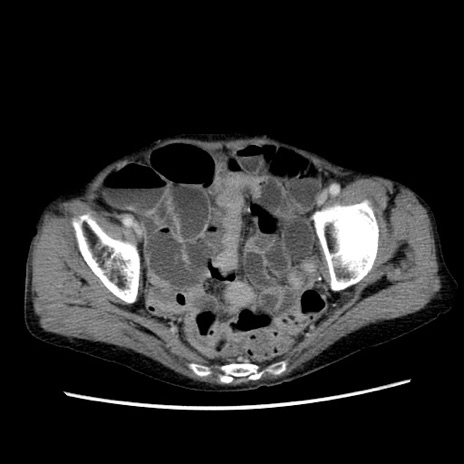

症例25(横断像)

【症例】80歳代女性

【主訴】胸のつかえ感

【現病歴】約9時間前に食後から胸のつかえた感じあり、嘔吐あり、来院。

【既往歴】胃癌(全摘)、胆摘、虫垂炎

【身体所見】心窩部に圧痛あり、反跳痛なし。

【データ】WBC 5700、CRP 0.05